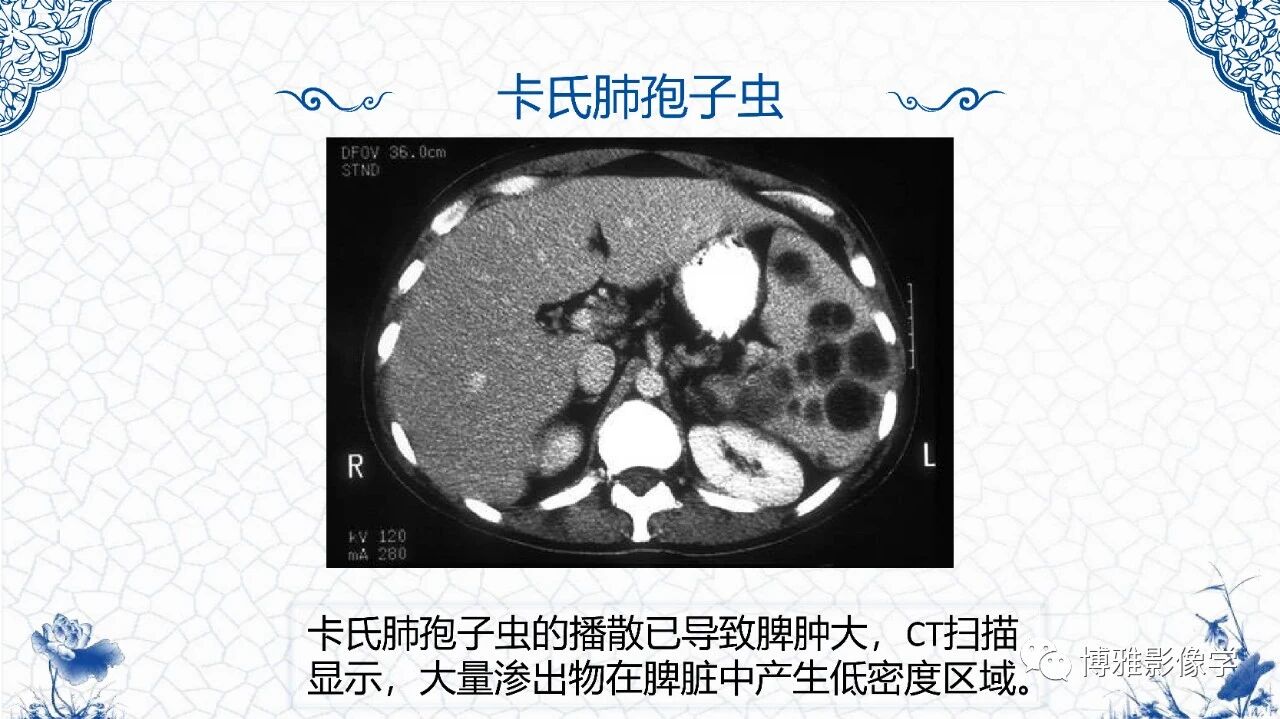

脾脏非肿瘤影像诊断